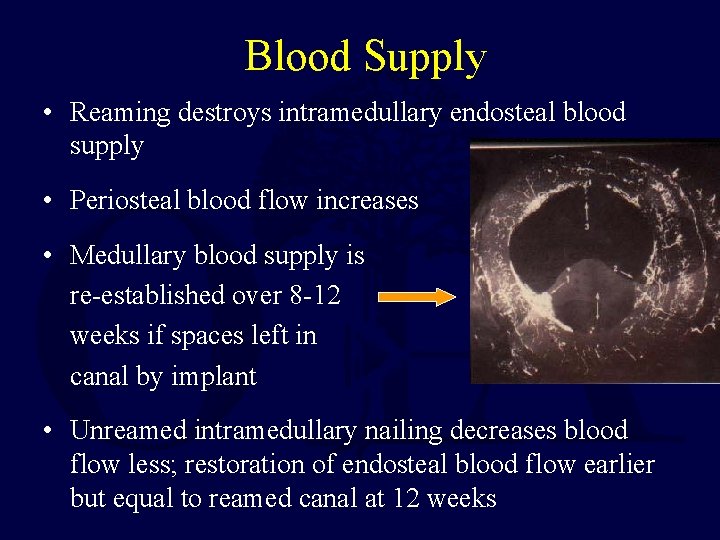

Blood Supply • Reaming destroys intramedullary endosteal blood supply • Periosteal blood flow increases • Medullary blood supply is re-established over 8 -12 weeks if spaces left in canal by implant • Unreamed intramedullary nailing decreases blood flow less; restoration of endosteal blood flow earlier but equal to reamed canal at 12 weeks